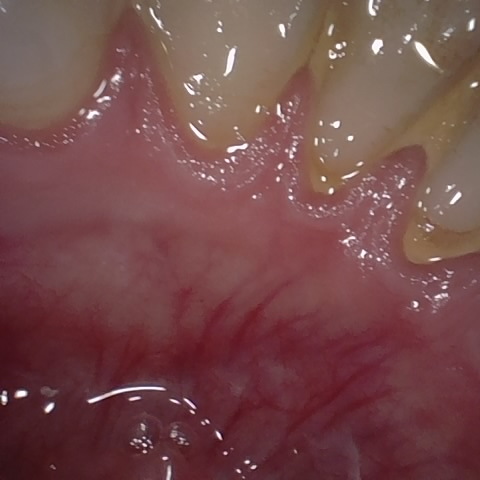

Annotated as "Bad"